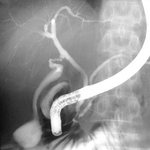

Typical endoscopic retrograde cholangiopancreatography findings in a patient with PSC: multi-focal strictures of the intra- and extrahepatic bile ducts

Dr Kris Kowdley's collection